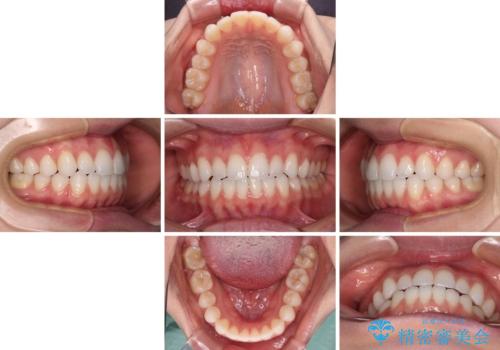

上下前歯が接触しない オープンバイトをインビザラインで改善

上下の奥歯を圧下させるようにすることで、前歯を接触させるように計画しました。

上下の隙間に舌が入り込むことがオープンバイトの原因であったため、舌の筋肉のトレーニングも並行して行い、後戻りの抑制を図りました。